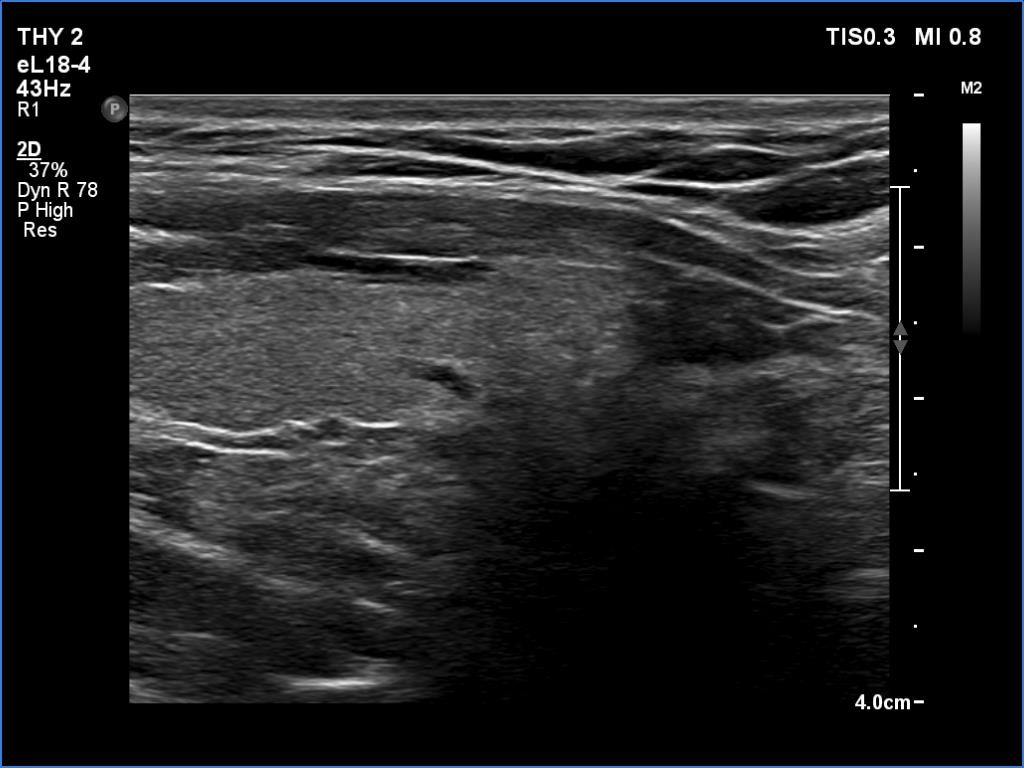

Right lobe, longitudinal scan

Left lobe, longitudinal view. The hypoechoic lesion is located just under the lower pole of the thyroid.